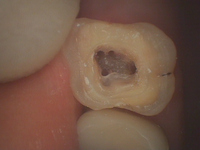

右上第1大臼歯の根管治療です。

穴が4つ空いているのが確認できると思います。

この穴はが神経の部屋の入り口で、この入口をキチンと明示することが根管治療において大切とされています。

上顎の第1大臼歯は通常3根管ですが、治療していて痛みが無くならないなど、症状が良くならない時にこの第4根管を見逃している事があります。注意しないといけません。